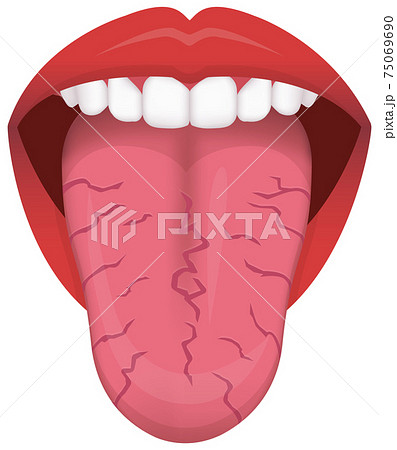

ベロ亀裂 (458 無料画像)

舌に亀裂がある カンジダ症 カンディダ 先天性病理学 — ストック写真 © natali_ploskaya430965280。

ひび割れた舌のイラスト素材105451846- PIXTA。

細菌感染症の舌、舌はつぐみ、亀裂舌写真素材368053802Shutterstock。

溝状舌 こうじょうぜつ とは 溝状舌の痛みの原因と対処法。

細菌感染の病気舌、舌はツグミです。舌の傷します。亀裂舌の写真素材・画像素材 Image 66956292。

病気サイン?舌がひび割れる4つの原因。溝状舌・ドライマウスはどう治す?病院は何科?Medicalook メディカルック。

細菌感染の病気舌、舌はツグミです。舌の傷します。亀裂舌の写真素材・画像素材 Image 67152584。

細菌感染症の舌、舌はつぐみです。舌の傷。裂開舌写真素材502656769Shutterstock。